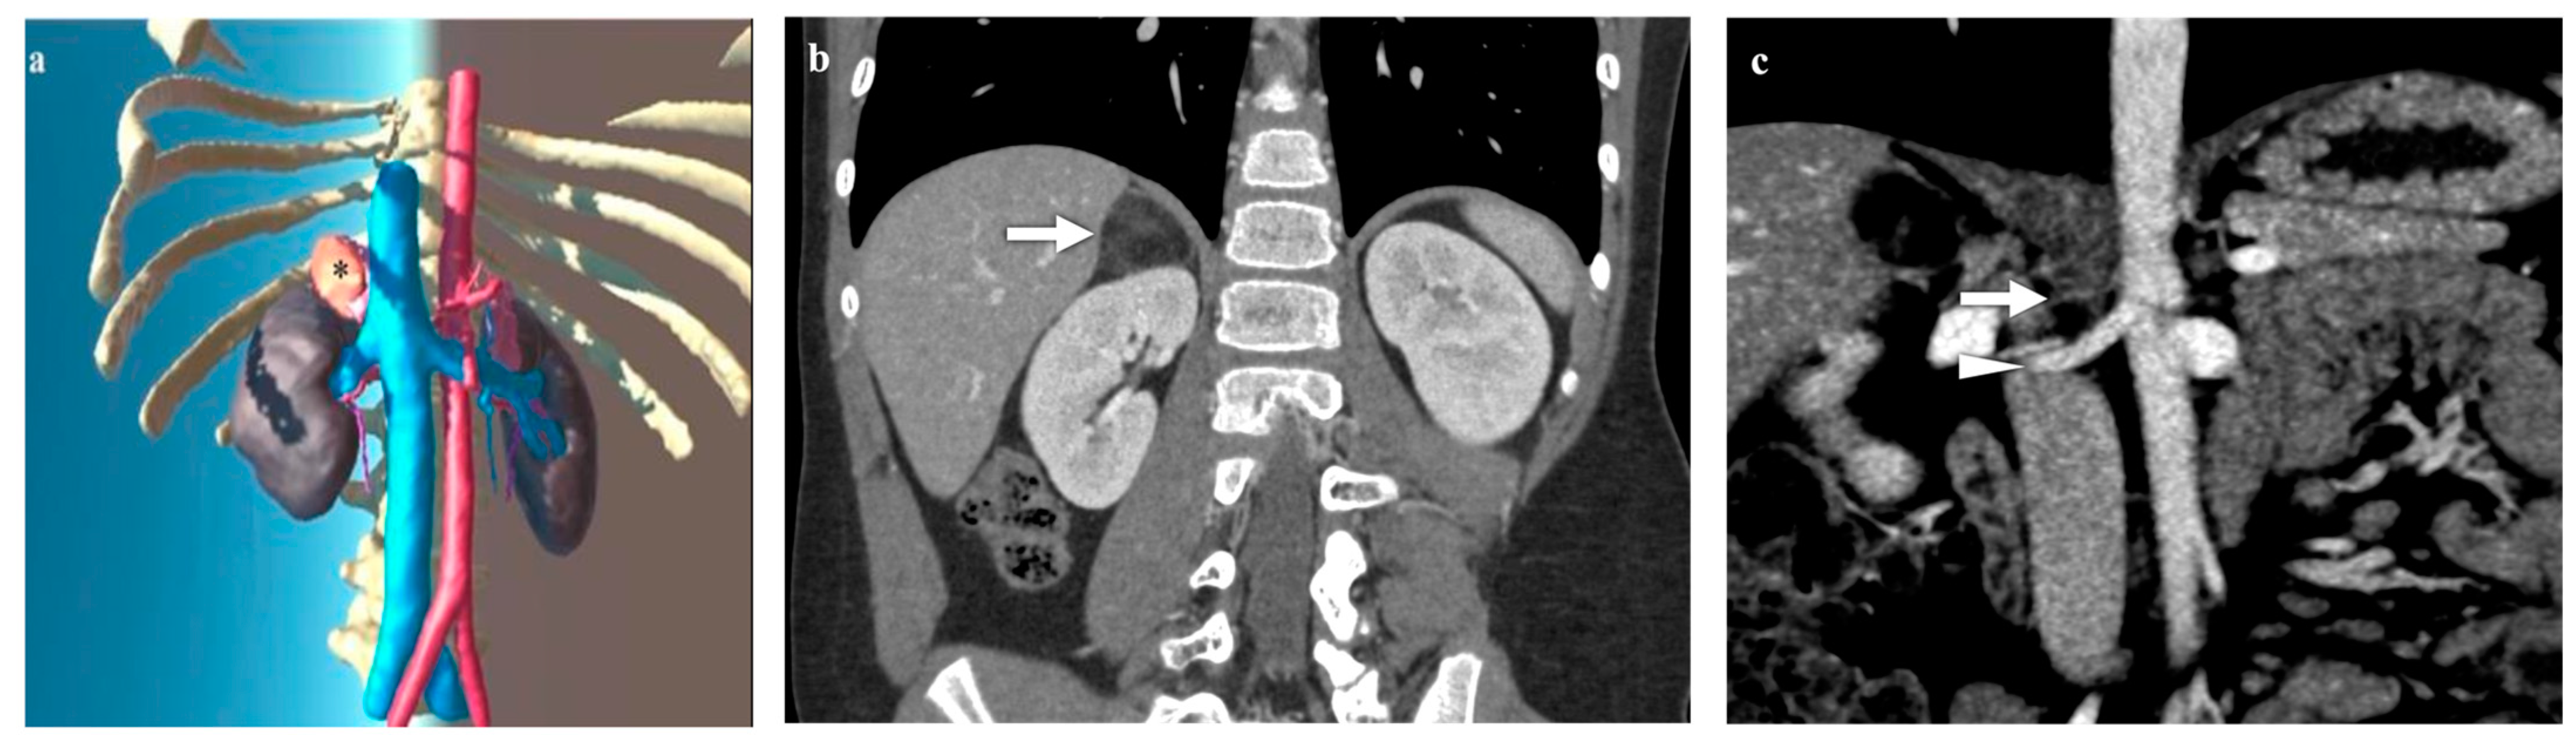

3.2. Adrenal Lesions

3.3. Kidney Lesions and Congenital Anomalies